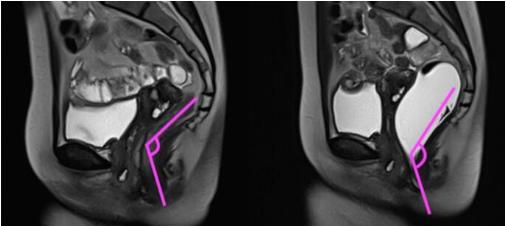

由于便秘存在多种类型,一般需要针对性采用不同检查方法进行鉴别和诊断。排粪造影,指的是使用 钡糊(一种影像学对比剂)直肠内注射模拟粪便,并通过影像学观察和分析患者整个排便的过程,从而评估排便相关盆底肌、直肠肛门及周围组织等排便活动中不同时间段的功能和重要解剖学参数变化的一种检查方法。磁共振排粪造影的优点是该检查可以进行实时动态的观察记录并且没有辐射,推荐用于怀疑为排便功能障碍型便秘患者的辅助检查,特别适用于存在形态和解剖学改变的便秘。排粪造影检查常常联合结肠传输实验、直肠肛门测压、球囊逼出实验等方法,用于慢性便秘的准确分类和分度,以便临床医生更为全面的掌握病情,制定更为合理的治疗方案。

▲ 图 8

排粪造影